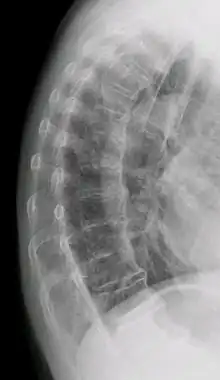

DISH in an 80 year old female, also with T11 fracture.

Diffuse idiopathic skeletal hyperostosis (DISH) is a condition characterized by abnormal calcification/bone formation (hyperostosis) of the soft tissues surrounding the joints of the spine, and also of the peripheral or appendicular skeleton.[1] In the spine, there is bone formation along the anterior longitudinal ligament and sometimes the posterior longitudinal ligament, which may lead to partial or complete fusion of adjacent vertebrae. The facet and sacroiliac joints tend to be uninvolved. The thoracic spine is the most common level involved.[2] In the peripheral skeleton, DISH manifests as a calcific enthesopathy, with pathologic bone formation at sites where ligaments and tendons attach to bone.

DISH is diagnosed by findings on x-ray studies. Radiographs of the spine will show abnormal bone formation (ossification) along the anterior spinal ligament. The disc spaces, facet and sacroiliac joints remain unaffected. Diagnosis requires confluent ossification of at least four contiguous vertebral bodies.[2] Classically, advanced disease may have "melted candle wax" appearance along the spine on radiographic studies.[13] In some cases, DISH may be manifested as ossification, or enthesis, in other parts of the skeleton.